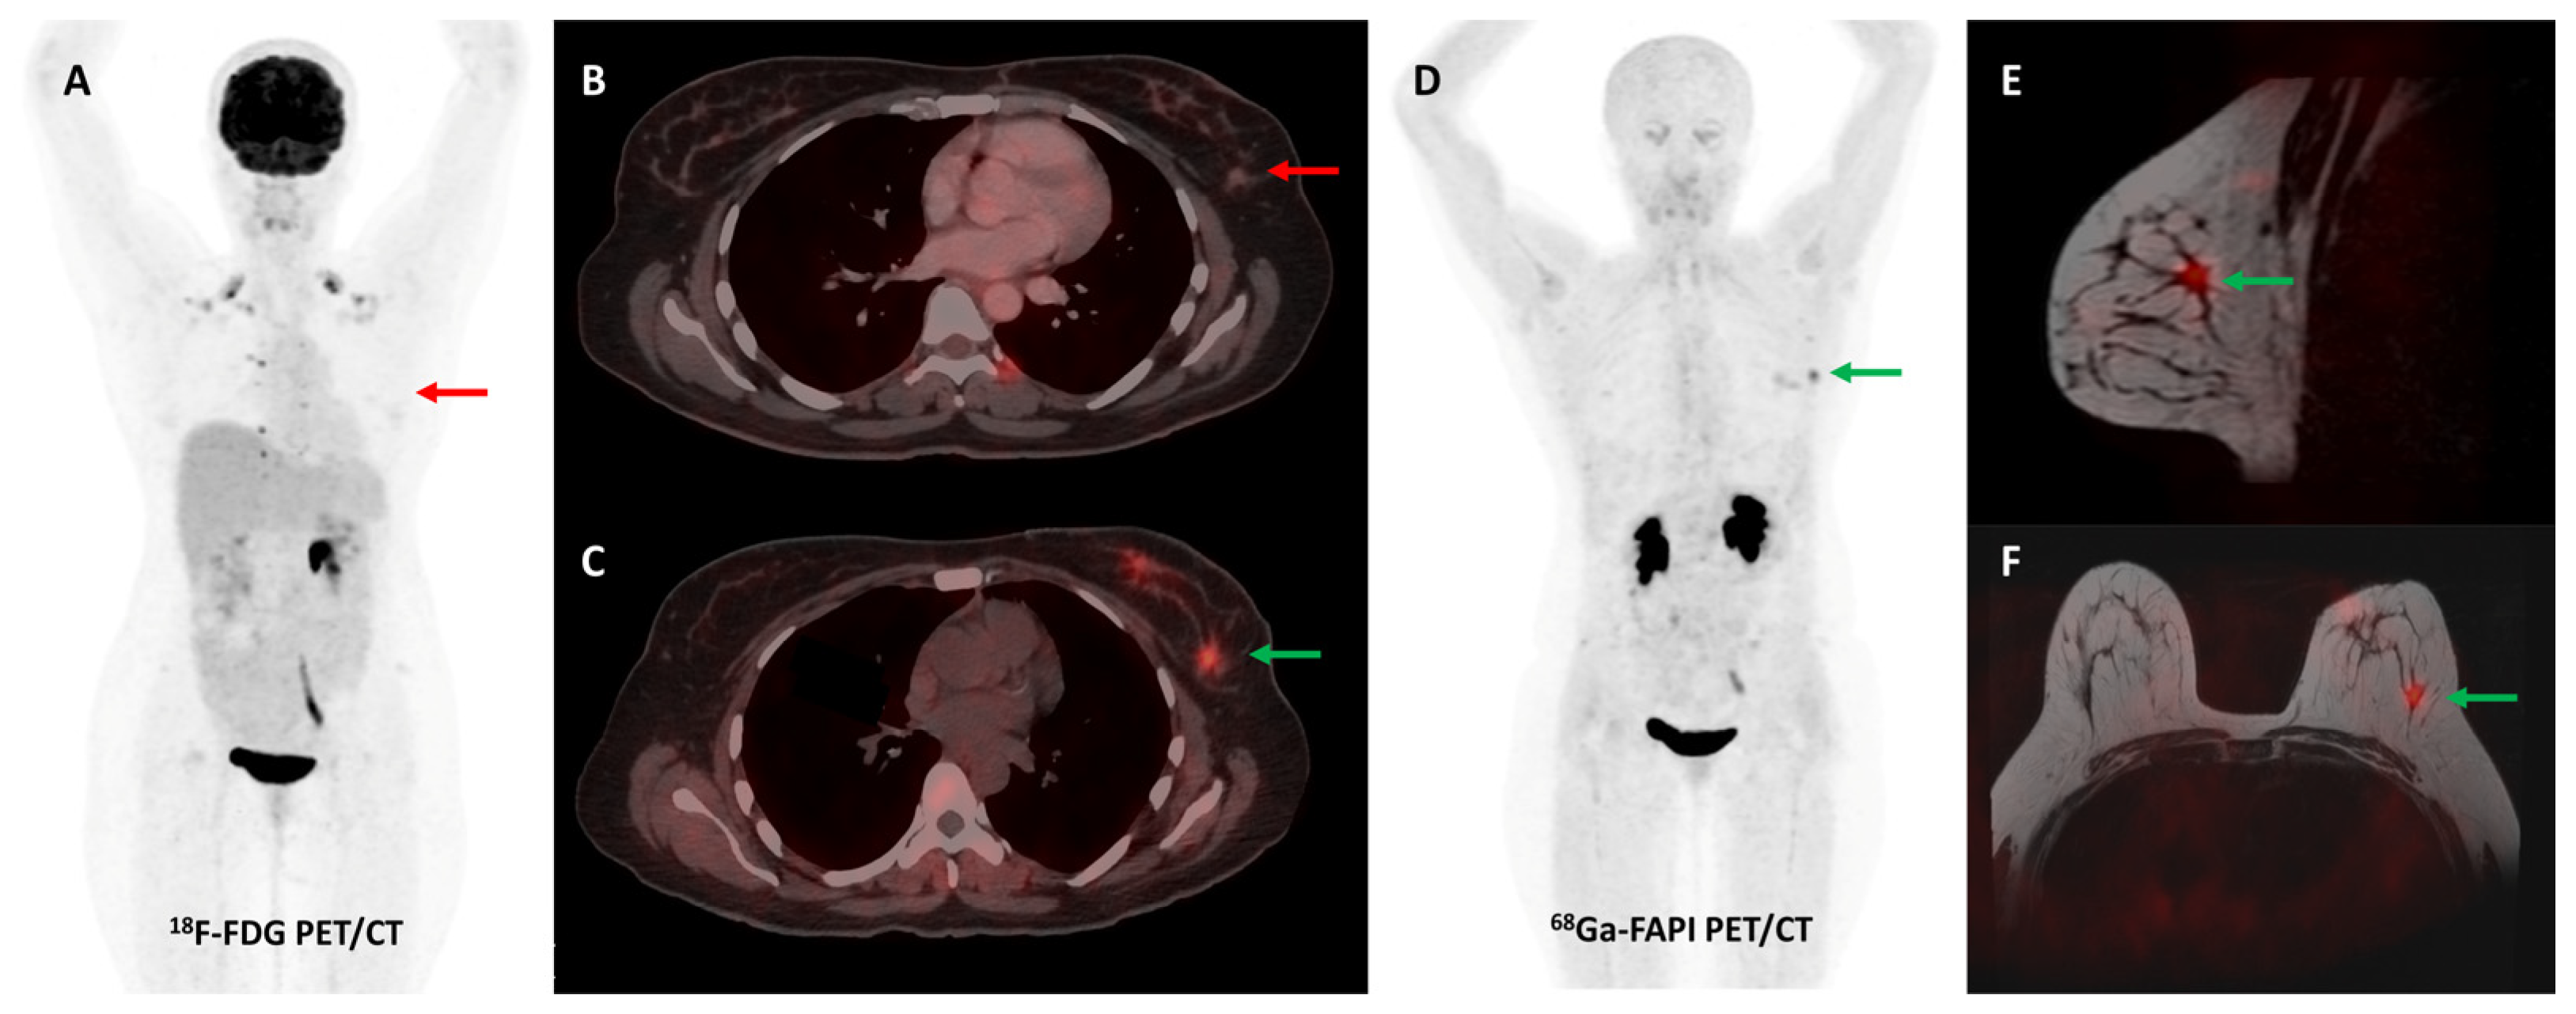

Activation of CAFs, particularly in the early development phase, leads to FAP overexpression both in tumor cells and the surrounding stromal component in CRC and other GI malignancies [72]. A higher degree of FAP expression is associated with higher tumor grade, invasiveness, and poor prognosis in CRC [73]. The first real-world clinical experience with FAP-targeted PET imaging (using either [68Ga]Ga-FAPI-04 or [68Ga]Ga-FAPI-46) in lower GI tract malignancies was reported by a German group. They found significant tracer uptake in anal cancer and liver metastases, with the TBR of most lesions being greater than 3. TNM staging was altered in 50% of the treatment-naïve patients and additional findings were picked up in 47% of patients with metastases. FAPI PET/CT improved TVD in a majority of patients being planned for radiotherapy (RT) [74]. Kömek et al. performed a head-to-head comparison of [68Ga]Ga-FAPI-04 and FDG PET/CT in 39 CRC patients. They found that FAPI PET/CT had higher sensitivity and specificity in the detection of primary lesions and lymph nodal metastases [75]. Pang et al. compared the diagnostic performance of [68Ga]Ga-FAPI-04 and FDG PET/CT in 35 patients with CRC, gastric and duodenal cancers. Overall, FAPI PET/CT had better sensitivity than FDG PET/CT for the detection of primary tumors (100% vs. 53%, respectively, p = 0.004), nodal (79% vs. 54%, p = 0.001), and distant metastases (89% vs. 57%, p = 0.001). FAPI PET/CT led to upstaging of the clinical TNM stage in 21% of the treatment-naïve patients [76]. Lin et al. reported the additional utility of [68Ga]Ga-FAPI-04 PET/CT in monitoring response to treatment in gastric carcinoma [77]. One such demonstrative case of gastric cancer is presented in Figure 3 and Figure 4.

Figure 3.

FDG and [68Ga]Ga-FAPI-04 PET/CT images in a 42-year-old woman with biopsy-proven gastric adenocarcinoma. The primary lesion in the stomach showed no abnormal FDG uptake ((A,C)—red arrows) with intense [68Ga]Ga-FAPI-04 tracer avidity ((B,D)—green arrows). FAPI PET/CT revealed a tracer avid hypodense lesion in segment V of the liver ((B,F)—green arrows), which was not picked up on FDG PET/CT ((E)—red arrow), leading to upstaging of disease. Additionally, the uterus showed no abnormal FDG uptake ((G)—red arrow) but had diffuse intense FAPI uptake ((H)—green arrow), which was interpreted as physiologic/benign uptake.

Figure 4.

Incremental role of [68Ga]Ga-FAPI-04 PET/CT over FDG PET/CT in a 42-year-old woman with metastatic gastric adenocarcinoma for post-chemotherapy response assessment. Baseline (A) and follow-up (C) FDG PET/CT scans did not reveal significant abnormal tracer uptake in the primary and metastatic lesions. Baseline [68Ga]Ga-FAPI-04 PET/CT (B) showed tracer avid gastric primary (green arrow), abdominal lymph nodes (orange arrow), and solitary liver metastasis (red arrow). Post-chemotherapy [68Ga]Ga-FAPI-04 PET/CT (D) demonstrated minimal tracer avidity in the gastric primary (green arrow) with resolution of tracer avidity in the abdominal lymph nodes (orange arrow) and liver lesion (red arrow), suggesting a favorable response to treatment.